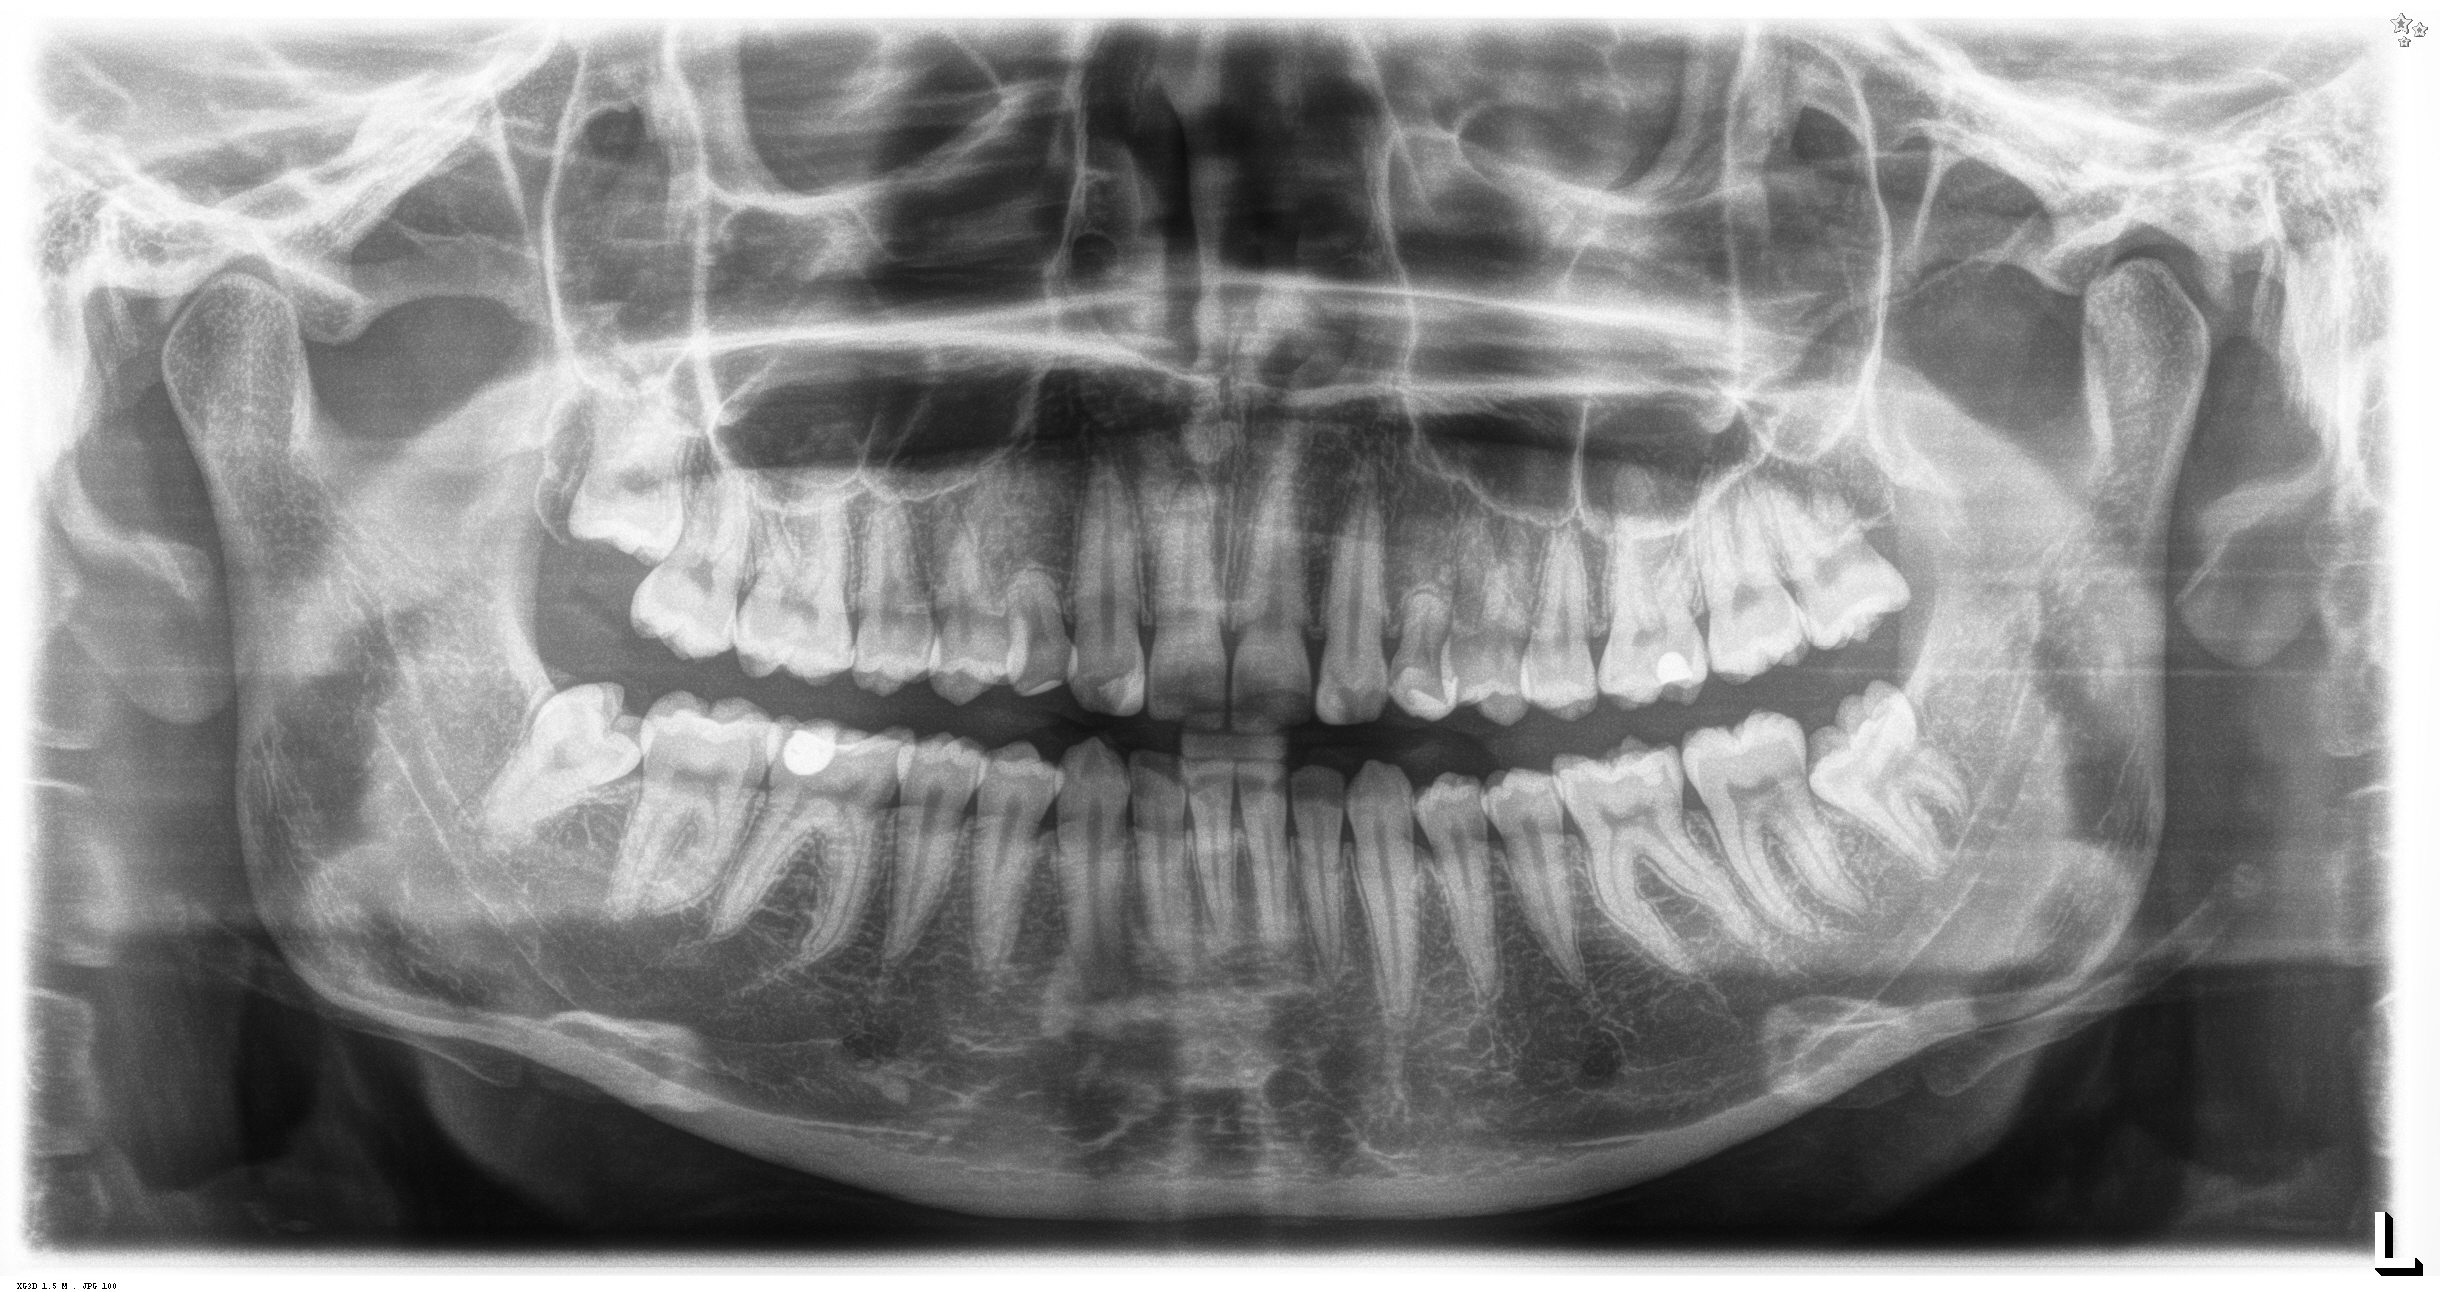

OPTG eli koko leuan rtg kuva alkutilanteesta